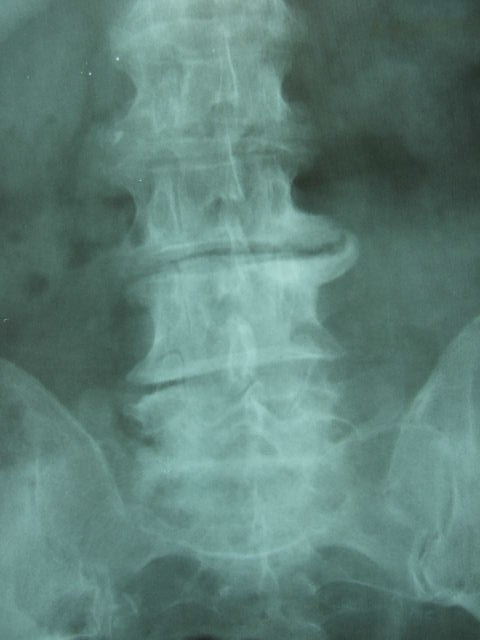

Artrosis lumbar con pinzamiento.

Artrosis lumbar